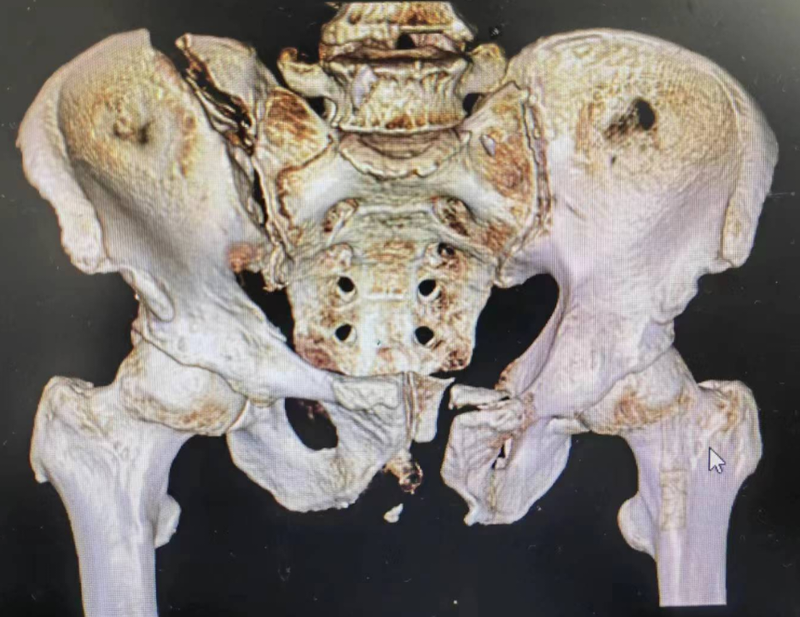

花季少女骨盆撞歪了,UCRT骨盆復(fù)位架閉合復(fù)位顯神奇!

一18歲年輕花季少女不小心車禍傷,骨盆被撞成嚴重畸形,右側(cè)骨盆嚴重向內(nèi)向上移位,骨盆環(huán)不圓了!6月1日在UCRT骨盆復(fù)位架閉合復(fù)位復(fù)位后骨盆環(huán)非常圓,采用骶髂螺釘固定和前方經(jīng)皮外架固定患者無傳統(tǒng)手術(shù)方式大切口,創(chuàng)傷小,以后無瘢痕骨盆復(fù)位架閉合復(fù)位技術(shù)開展起來,筆者目前在全省及全國七八十家醫(yī)院開展和普及這種手術(shù)方式,不忘初心,普及新技術(shù),造?;颊?!